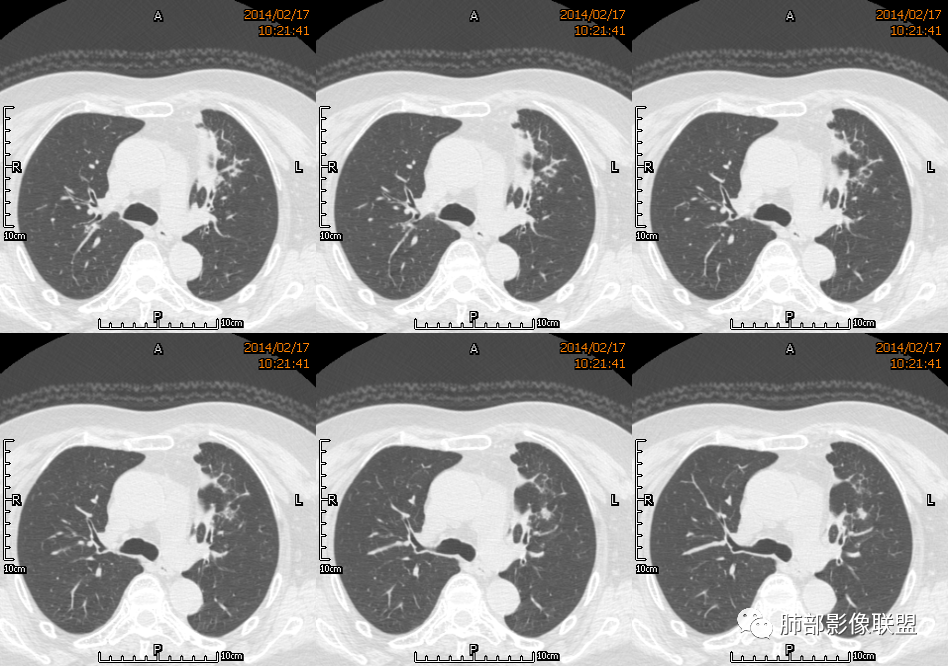

红星: 老年女性,咳嗽咳痰10天,痰中带血4天。左肺上叶前段胸膜下肿块影,沿支气管方向走行以膨胀生长为主,局部有收缩改变,支气管血管绝断,中间有小片状的坏死及小的空洞影,增强扫描病灶明显的强化,病灶周围网格状的小叶间隔增厚。拟左肺上叶前段浸润型腺癌并癌性淋巴管炎。鉴别诊断结核肉芽肿。

傅昌瑜: 老年女性,咳嗽咳痰10天,痰中带血4天。左肺上叶前段胸膜下肿块影,沿支气管方向走行,膨胀生长为主,局部边缘似有收缩改变,中间有小片状的坏死,支气管进入,增强扫描病灶明显的强化,血管走形较自然(血管漂浮征?),病灶周围网格状的小叶间隔增厚。考虑淋巴瘤可能性大,注意鉴别炎性肉芽肿及肺腺癌。

水晶石头: 患者老年女性,咳嗽咳痰10天,痰中带血4天余。查血常规白细胞低;肿瘤标志物、凝血功能正常;血生化:蛋白低;C反应蛋白、血沉稍升高。胸部CT:左肺上叶前段胸膜下沿气管支气管走形肿块影,长轴与胸膜平行,见分叶、毛刺、支气管截断、空泡征象。增强明显强化,且见血管造影征及病灶内小灶低密度坏死区。左肺上叶尖后段见一结节灶。综合考虑恶性病变可能大,腺癌或淋巴瘤可能。鉴别诊断肺脓肿。

尘缘: 老年女性,咳嗽咳痰10天,痰中带血4天,白细胞及中性粒明显减低,轻度贫血。影像表现:左上叶肿块,边缘膨隆,局部平直,支气管稍扩张,进入后远端堵塞,内见小空洞及不规则坏死区,增强后强化明显,坏死边界较清,并见环状强化区,内部血管走行自然,周围见小叶间隔增厚呈大网格征。初步诊断:慢性炎性伴脓肿形成及肉芽组织增生。鉴别淋巴瘤及腺癌,先抗炎治疗后复查或直接穿刺明确。

王崇军: 老年女性,咳嗽咳痰10天,痰中带血4天。左肺上叶前段胸膜下 肿块影及段形态密度增高影,沿支气管方向走行,膨胀生长为主,局部有收缩改变,支气管进入并闭塞,中间有小片状的坏死及小的空洞影,空洞漂浮在坏死边缘,增强扫描病灶明显的强化,坏死边界清楚,似乎有轻度强化环,病灶周围网格状的小叶间隔增厚及小结节影,外侧胸膜呈糊墙改变。考虑为肺脓肿,这么大的病灶,竟然没有发烧,白细胞低,CPR轻度升高,均与脓肿不符,所以恶性待排,短期抗炎治疗后复查,病灶没有变化,脓肿就可以排除,恶性基本可以确定。

空格: 临床特点:老年女,血糖略高,低蛋白血症,白细胞低,提示有免疫下降的存在。机会性感染存在机会。黄浓痰一般常见于炎性病变,痰中带血则肿瘤多见,两厢pk,觉得黄脓痰胜,除非肿瘤继发感染一般不会黄脓痰。影像:一 、良性征像:1.病灶整体是个尖端指向肺门的三角形病灶;2.胸膜平直,胸膜外少量液体糊墙;3.支气管未见明显截断,内壁毛糙?4.近端支气管弥漫性增厚,结核脓痰咯出,看做引流支气管;5.多个层面病灶呈直边征,多角征,无明显分叶;6.病灶内坏死边缘光整,伴小气泡。小叶间隔增厚光滑锐利,无结节,不太像癌淋。二、恶性征像:部分层面向胸膜外突,略有占位效应。总体考虑感染性病灶,霉菌可能。结核抗体阴性,可以排除?

刘和林: 老年女性,咳嗽咳痰10天,痰中带血4天。左肺上叶前段胸膜下 肿块影,沿支气管方向走行,膨胀生长为主,局部边缘似有收缩改变,中间有小片状的坏死,坏死区内见小气泡,支气管进入、部分填充、部分末端稍显扩张,增强扫描病灶明显的强化,周围肺不干净,其上肺见小叶间隔增厚。肺癌、淋巴瘤、炎性肉芽肿?肺癌:支气管末端稍扩张,周围类似树芽征改变,不太符合。淋巴瘤:数个小气泡,明显强化,周围树芽征样改变,不太符合。

2.左肺上叶前段胸膜下块状影,不规则呈“逗点样”延向肺门区,边界清楚,未见分叶、毛刺及张力,表面不规则棘突,状如“火焰”或“日冕”。相邻胸膜增厚,未见栽赃、卫星病灶。

3.病灶密度不均,中央坏死液化并见气泡影,支气管及血管贴边进入,较均匀环形强化(显示多层结构),未见明确壁结节。

3.病灶易坏死液化,环形强化,支气管及血管贴边进入,“火焰”样边缘轮廓,更符合炎性块影的特点。

4.单发脓肿,临床中毒症状不重,短期多见于肺炎克雷比杆菌感染,亚急性病程的还应排除奴卡菌感染。